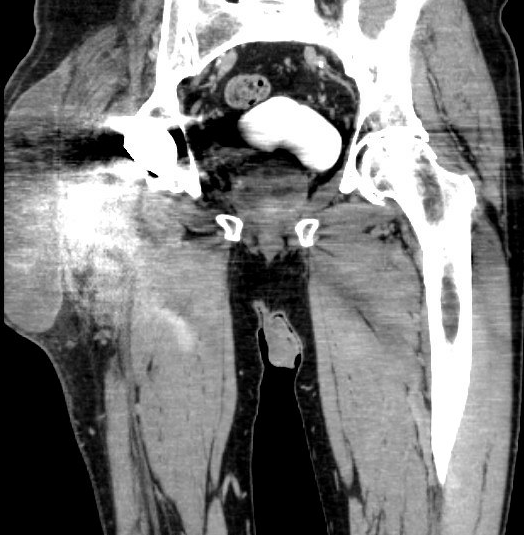

MRI / CT

CT demonstrating large fluid collection around THA